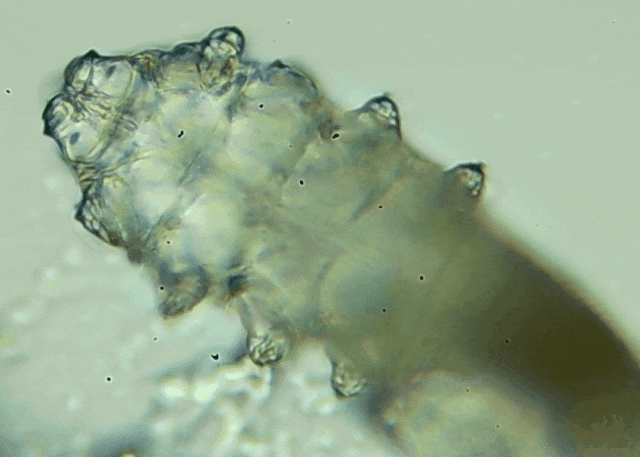

眼睛里螨蟲(chóng)主要是指蠕形螨,它們是一種肉眼難以看見(jiàn)的微小寄生蟲(chóng),通常寄居在人體的毛囊和皮脂腺中,睫毛根部的毛囊以及瞼板腺內(nèi)就是他們的常住地,這里溫暖且油脂豐富,為螨蟲(chóng)提供了理想的生活環(huán)境。